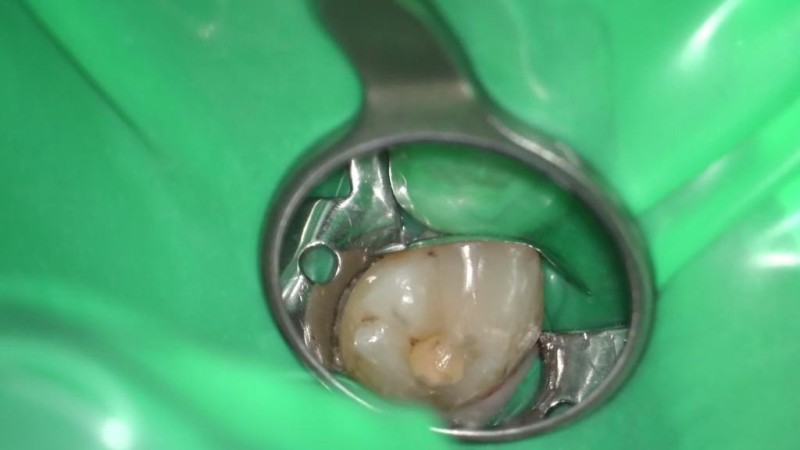

О стоматологе

Проводит лечение на эксклюзивном микроскопе Карла Цейса (Zeiss Extaro 300) с полным сопровождающим фотопротоколом. За счет многократного увеличения и оснащения микроскопа специальным светом, Татьяна Андреевна достигает совершенного подбора оттенков зуба при реставрациях, а также может диагностировать кариес на самых начальных стадиях, что невозможного сделать без микроскопа. Регулярно принимает участие в международных стоматологических форумах и конгрессах. Общительный и позитивный человек, а в работе – отличается тщательностью и аккуратностью. Ее профессиональное кредо – делать так, как хотела бы сделать для самой себя. С энтузиазмом увеличивает свой багаж профессиональных знаний и опыта. Стоматолог-терапевт. Общительный и позитивный человек, а в работе – отличается тщательностью и аккуратностью. Ее профессиональное кредо – делать так, как хотела бы сделать для самой себя. С энтузиазмом увеличивает свой багаж профессиональных знаний и опыта.

Бойцова Татьяна Андреевна: портфолио (3)